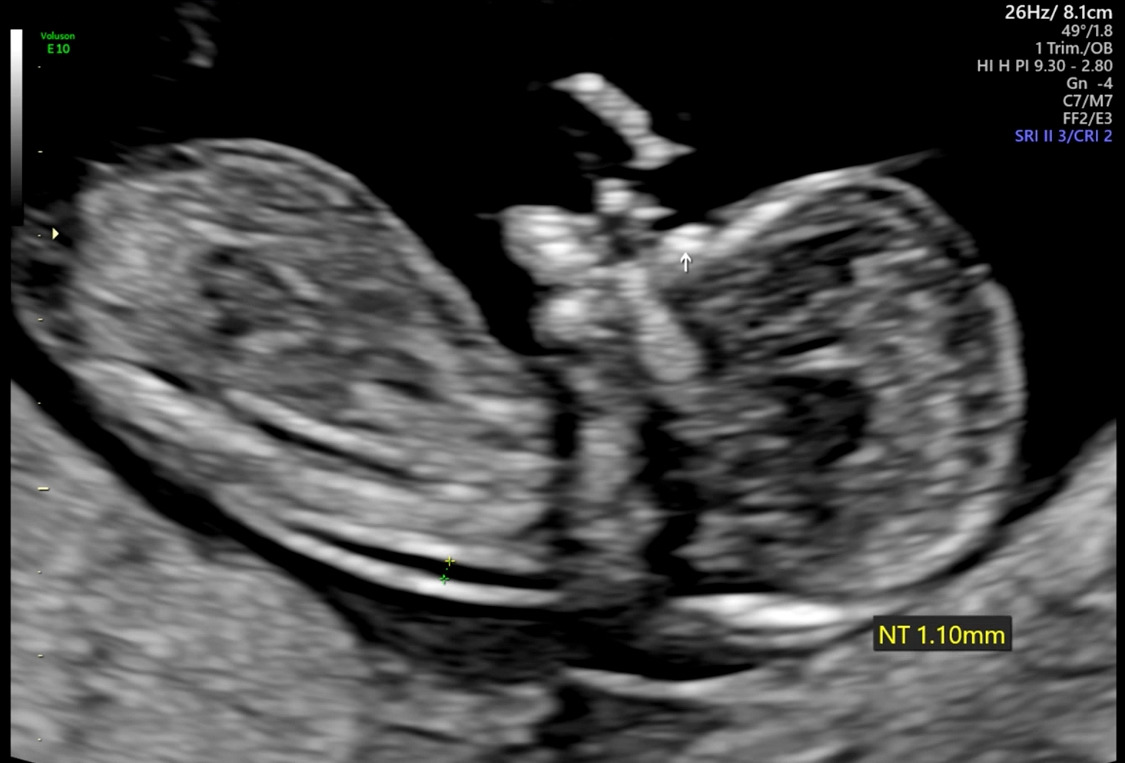

KakaoTalk_20220629_170123889.jpg NT와 화살표가 가리키는 코뼈

다운증후군의 마커로서 코뼈 유무와 NT(목덜미 투명대, 자세한 내용은 https://brunch.co.kr/@the-cosmos/17 '다운증후군 산전검사에 대하여') 두께를 확인했다. 코뼈도 정상적으로 잘 보였고, 아기의 NT 두께는 1.1mm로 정상범위였다. 이제는 태반에 연결된 탯줄도 제법 잘 보이고, 얼굴 윤곽도 조금 보이는 듯했다. 양손과 양 발, 뇌부터 방광까지 현재 확인할 수 있는 장기까지 잘 확인하고는 써니의 첫 4D 초음파를 촬영했다. 지금까지 잘 있다가 검사가 끝나니 꼬물거리는 아기. 얼굴을 보여주지 않으려고 돌아 눕다가, 잠깐 정면을 보여줬다. 안녕 써니야!